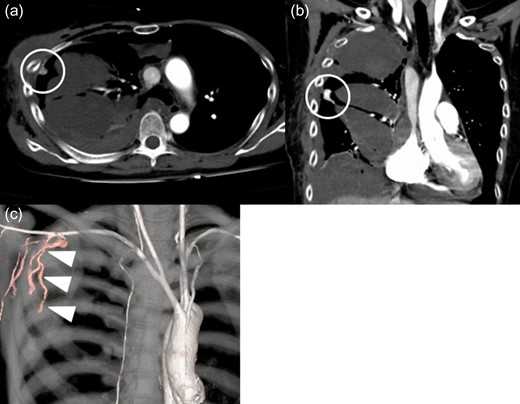

Contrast-enhanced computed tomography findings at 1 week. There is a tuberous enhancement in the right chest cavity near the fourth intercostal space (circle). Right lateral thoracic artery (arrow heads) connect to a tuberous enhancement. Axial view (a). Coronal view (b). Three-dimensional volume rendering computed tomography (c).

A 55-year-old woman with asymptomatic severe mitral regurgitation (MR) was referred to our department for surgical evaluation. Transthoracic echocardiography showed severe MR (Barlow type) and moderate tricuspid regurgitation. Mitral valve repair (triangular resection, chordal translocation and annuloplasty with a 34-mm CG Future Annuloplasty Band (Medtronic, Inc., Minneapolis, MN, USA)) was performed through the fourth intercostal space with a mini-thoracotomy approach (no adhesion in the pleural space), similar to that previously reported [1]. Tricuspid valve repair using a 28-mm Physio Tricuspid annuloplasty band (Edwards Lifesciences, Irvine, CA, USA) was done concomitantly. Before wound closure, hemostasis of the incision and port insertion site was confirmed by endoscopy. The patient was extubated in the operating room, with stable hemodynamics. We started warfarin on postoperative day 3. The right chest drain tube was removed on postoperative day 4. One week after the surgery, her blood pressure dropped with anemia. PT-INR was 3.11 at this time. Contrast-enhanced computed tomography (CT) showed hemothorax on the right side. There was a tuberous enhancement in the right chest wall, and it was considered to be the bleeding source (Fig. 1). A chest drain tube was placed again and EVT was then performed. A catheter was inserted from the femoral artery to the right axillary artery, and extravasation of contrast medium from the right lateral thoracic artery was confirmed by angiography (Fig. 2). The microcatheter was inserted into the right lateral thoracic artery, and coil embolization (Hilal Embolizing Microcoil 2 mm × 2 cm, Cook Medical Inc., Bloomington, IN, USA) and gelatin sponge injection (Serescue, Astellas Pharma, Tokyo, Japan) were performed (Fig. 3a). Hemostasis was confirmed by postprocedural angiography (Fig. 3b). There were no EVT-related complications. The patient was discharged without any complications on postoperative day 20.